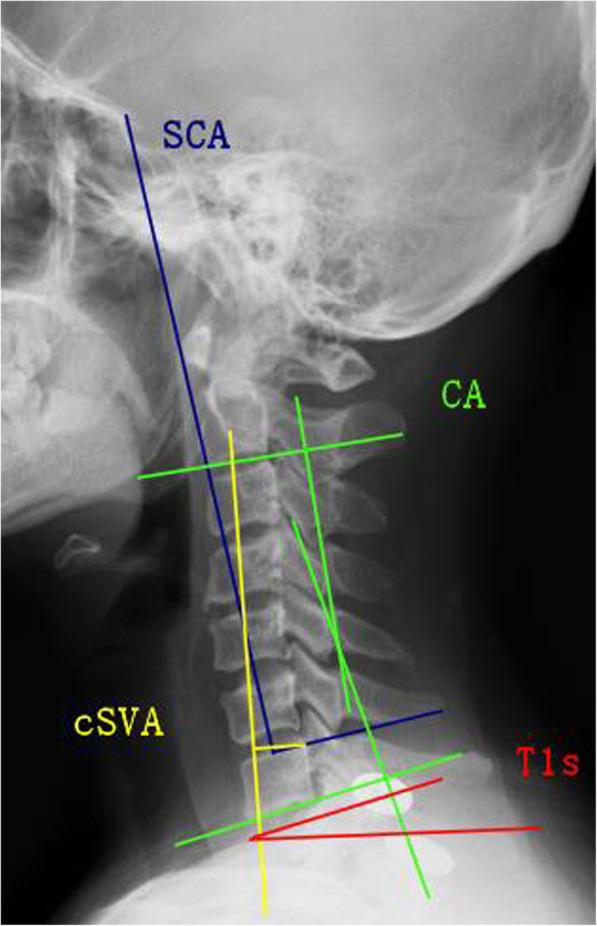

To study the impact of changes in spino-cranial angle (SCA) on sagittal alignment and to investigate the relationship between SCA and Neck Disability Index (NDI) scores after laminoplasty (LP) MATERIAL AND METHODS: In total, 72 patients with multilevel cervical spondylotic myelopathy (MCSM) after laminoplasty (LP) were retrospectively enrolled. Based on the optimal cut-off values of preoperative SCA, patients were classified into low SCA and high SCA groups. Radiographic data were measured, including spino-cranial angle (SCA), T1-slope (T1s), C2-7 lordosis (CA), T1s minus CA (T1sCA), and C2-7 sagittal vertical axis (cSVA). JOA and NDI scores were both applied to assess postoperative and follow-up clinical efficacy. Pearson correlation coefficient and linear regression analysis were respectively calculated between radiographic data and between SCA and NDI.

The preoperative SCA was significantly correlated with T1s (r = - 0.795), CA (r = - 0.857), and cSVA (r = 0.915). A receiver operating characteristic (ROC) curve model predicted a threshold of SCA (value of 85.2°). At the follow-up period, patients with lower SCA had a higher T1s and CA and a lower cSVA, simultaneously accompanied by greater △T1s, △CA, and △cSVA. The linear regression model demonstrated that SCA in the higher group was positively correlated with NDI, and patients with higher SCA had worse NDI scores (pre: p < 0.001; post: p < 0.001; F/U: p = 0.003) and greater changes of NDI (post: p < 0.010; F/U: p = 0.002).